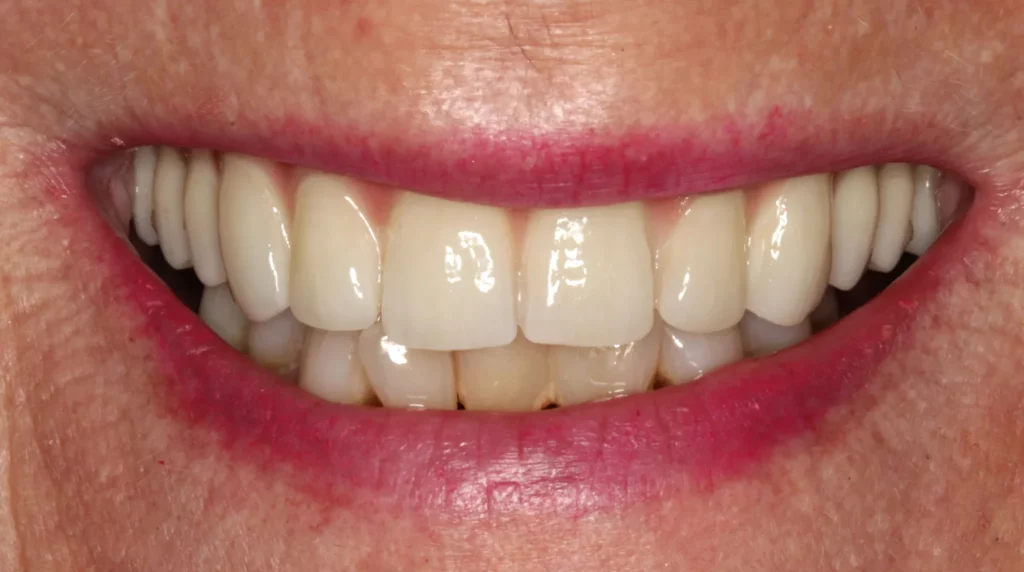

One New Year’s Eve, we received a phone call from a distressed lady who said her top front bridge had fallen out unexpectedly. Regrettably, the two teeth that supported the bridge had decayed and couldn’t be fixed. The patient wanted to avoid wearing a long-term denture and had always longed for a better smile. She was very self-conscious when smiling, and like many people, having her photo taken was not her favourite event.

To achieve smile symmetry, the gum was recontoured around the adjacent teeth while others had gum grafts placed to reduce the speed of gum recession. Both the health and appearance of the smile were addressed.